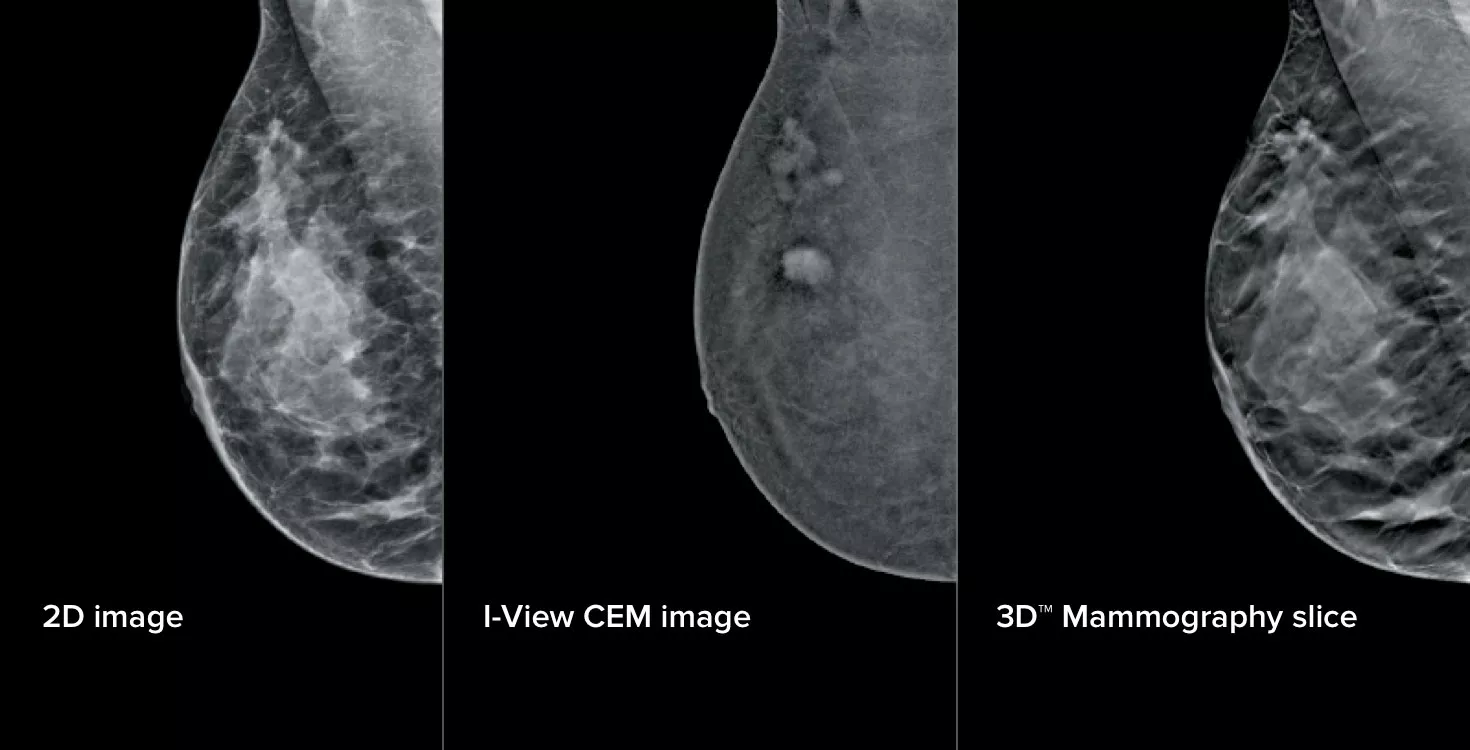

Tre bilder från en kompression

Denna programvara samlar in både anatomisk och funktionell information i en enda undersökning genom att utnyttja förmågan att tillhandahålla 2D-, kontrast- och tomosyntesbilder med bara en kompression.1

I-View CEM-avbildning är en enkel uppgradering för alla Selenia® Dimensions®*- och 3Dimensions™-system, vilket ger en effektiv väg till utökade diagnostiska möjligheter för avbildning av bröst.